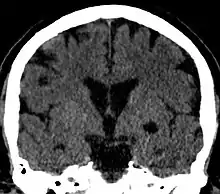

Choroidal fissure cyst

Coronal CT of the brain showing a choroidal fissure cyst

A choroidal fissure cyst is a cyst at the level of the choroidal fissure of the brain. They are usually asymptomatic and do not require treatment.